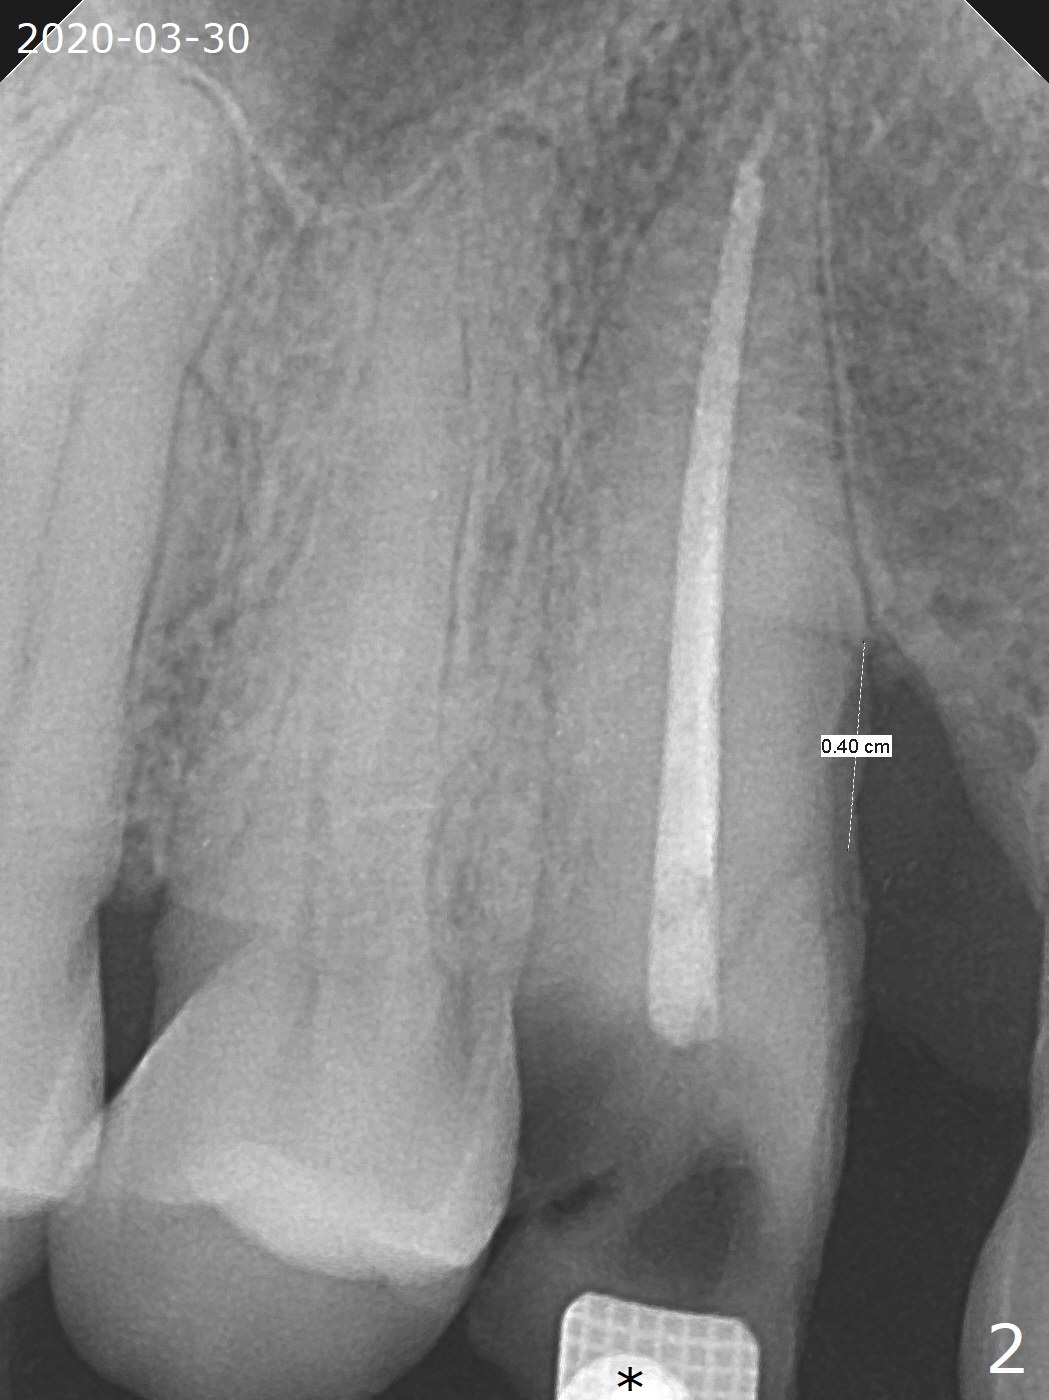

A 62-year-old man had traumatic root fracture at #6 in his teen. The tooth remained asymptomatic until his fifties. Following root canal therapy (Fig.1), the tooth is orthodontically extruded (~ 5 years, Fig.2 (*: bracket)) with apparent disappearance of the infection. The bone distal to #7 seems to increase in height (Fig.3, as compared to Fig.1) and in density (Fig.4). Bone graft could be placed for regeneration with PRF or GEM21S (Fig.5 red (between #6 and 7), pink (buccal to #7 or coronal to the fracture line) circles). With extrusion, the oblique fracture line is more than half or two third supragingival (Fig.6). In spite of severe bone loss, exostosis is present (Fig.7 (mesiobuccal view) E) so that bone graft could be placed palatal to it (Fig.8 red). In case the tooth is non-salvageable, immediate implant will be placed with guide (Fig.9,10). Move lingual button as apical as possible (Fig.12) and make occlusal clearance. Continue extrusion until all of the crack is exposed without deep pocket.